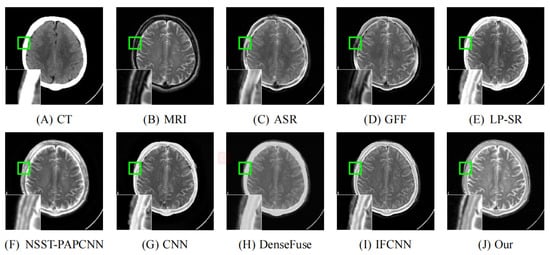

As illustrated in Figure 8, Figure 9, Figure 10, Figure 11 and Figure 12, we select fusion results of five pairs of images as the visual comparison. Among these figures, source images (CT and MRI) are shown in (A) and (B). (C) to (J) are fusion results obtained by various fusion methods. Every image has an enlarged subimage in the lower-left corner that is useful for visual assessment.

Although it’s hard to assess the visual effects of these results accurately, significant differences are observed. Figure 8, Figure 9, Figure 10, Figure 11 and Figure 12 show CT images that are high-resolution in dense structures such as bones and implants but low-resolution in soft tissues. MRI images can offer high-resolution edge and anatomical information for soft tissues. However, the other seven methods are affected to varying degrees by the low-resolution soft tissues information of the CT images. It may cause the fused image with fewer details and blurred contours. ASR is a TD-based method that calculates weight maps by some pre-trained dictionaries. The results of ASR have a low contrast ratio and halo effect. As illustrated in Figure 8, the enlarged subimage of ASR has a low contrast ratio and the bone of fused image has a black halo. GFF is a TD-based method. This method decomposes the source images into base layer and detail layer. Then, multiple filters, such as average filter and guided filter, are utilized to merge the features. Thus the contrast is poor in the fused images obtained by GFF. Figure 9 shows that a part of bone in the enlarge subimage is missing. LP-SR and NSST-PAPCNN are mixed fusion methods, which employ MST to decompose the source image and then use different strategies to fuse the high-frequency features and the base features, respectively. LP-SR employs Laplacian pyramid to decompose the source image and then uses the “choose max” rule to fuse the high-frequency features. The multi-scale decomposition and activity level measurements are required for MST-based fused results. This may result in the loss of some details. For example, in Figure 8 and Figure 11, the fused image of LP-SR is more close to the CT image and lose the detail and structure information of MRI image. NSST-PAPCNN employs NSST to decompose the source image and then uses PAPCNN to fuse the detail textures. The soft tissue detail of fused image by NSST-PAPCNN is close to our fusion result, whereas is fuzzier in the edge detail, such as the enlarged part of Figure 11. CNN, DenseFuse and IFCNN are DL-based methods. However, CNN uses LP and GP to fuse the extracted features, which leads to the loss of details from MRI images. Similar to LP-SR, we can also observe the fused image of CNN lose the detail and structure information in the Figure 8 and Figure 11. Similar to our proposed method, DenseFuse uses an encoder-decoder architecture, but the l 1 N o r m strategy is used in the fusion block. This strategy may make the detail textures of fused images by DenseFuse be smoothed, which can be observed in all the five fused results. Different to our proposed method, IFCNN adds the fusion block to the training phase. It selects elementwise-maximum as the fusion strategy. However, the contrast is lower than our proposed method and the edge detail is not clear enough in the fused result by IFCNN. Overall, the comparison experiment demonstrates our method preserves more textual details and clearer edge information. In addition, due to the higher contrast, our fused images are friendly to human vision.

Figure 8. Fusion images of “Acute stroke speech arrest-7” by various methods. From (A) to (J): CT, MRI, ASR, GFF, LP-SR, NSST-PAPCNN, CNN, DenseFuse, IFCNN, Our proposed method.